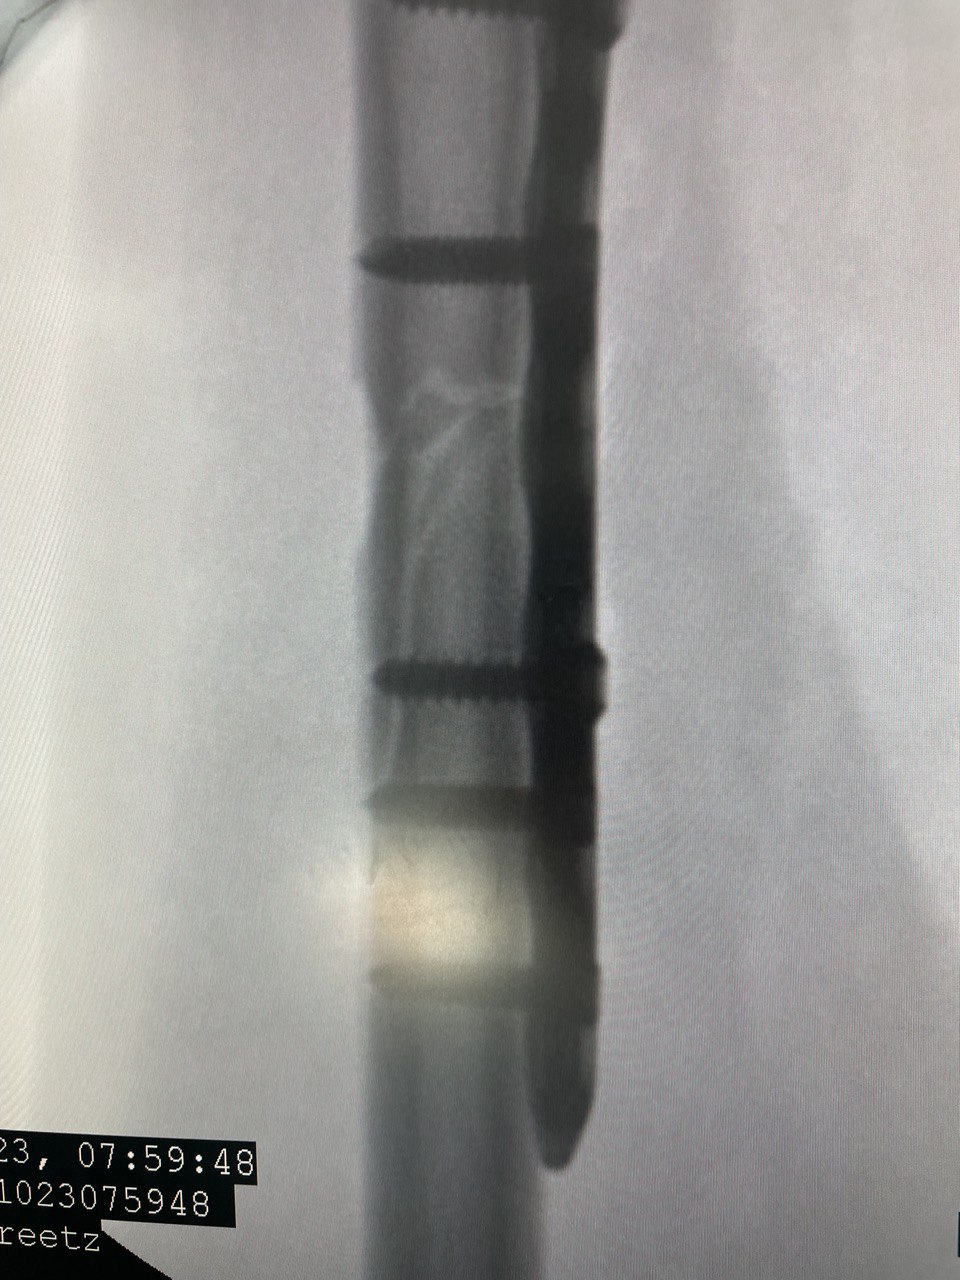

Клинический случай: перелом диафиза лучевой кости

Клинический случай с повреждением диафиза лучевой кости и последовательным контролем состояния.